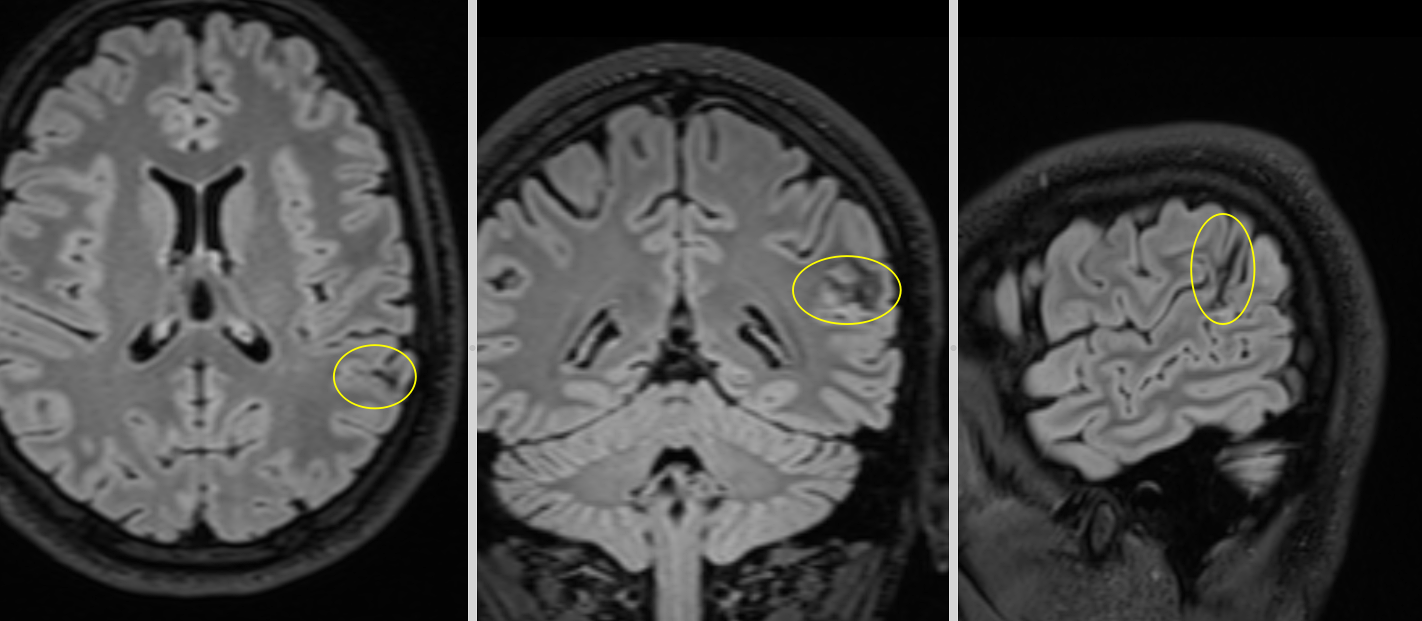

5. Tumora glioneuronală multinodulară și vacuolizantă (MVNT)

- Descoperită recent, frecvent diagnosticată prin RMN.

- Localizare: De obicei lob temporal.

- Aspect imagistic: Leziuni multinodulare neenhancement, bine delimitate.

- Clinic: Epilepsie.

- Tratament: Observație sau chirurgie dacă simptomatică.

- Grad OMS: 1

- Imagistică prin RMN: Aspecte caracteristice (leziuni corticale, fără edem semnificativ, fără contrast intens).